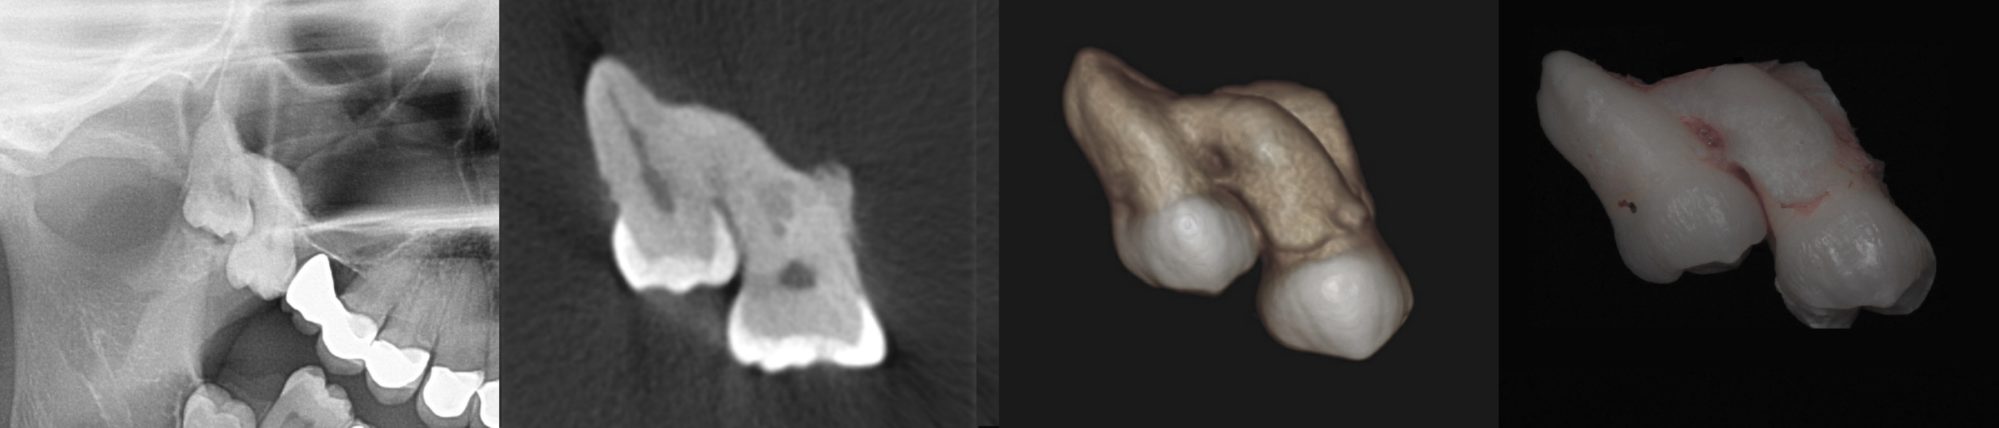

Chirurgicznym usunięciem zęba nazywamy zabieg ekstrakcji zęba lub jego fragmentu przy użyciu bardziej złożonych technik operacyjnych i zaawansowanego instrumentarium. Tych sposobów używamy w sytuacji, gdy mamy do czynienia z bardzo zniszczoną strukturą zęba, trudnym położeniem zęba czy też jego złamaniem w taki sposób, że pozostały fragment uniemożliwia prostą ekstrakcję.

Trzecie trzonowce (ósemki) górne i dolne, potocznie nazywane zębami mądrości, powinno się usuwać, gdy zaistnieją ku temu wskazania. Kwalifikujemy je do ekstrakcji, gdy nie rokują wyrżnięcia w prawidłowej pozycji, są przyczyną powtarzających się stanów zapalnych, powodują problemy ze zgryzem, na zdjęciach rentgenowskich widoczne są wokół ich koron kieszenie kostne lub są przyczyną rozległych torbieli zawiązkowych.

W sytuacji zęba zatrzymanego lekarz decyduje o jego chirurgicznym usunięciu. Po wyjęciu zęba oczyszcza zębodół i zabezpiecza szwami ranę.